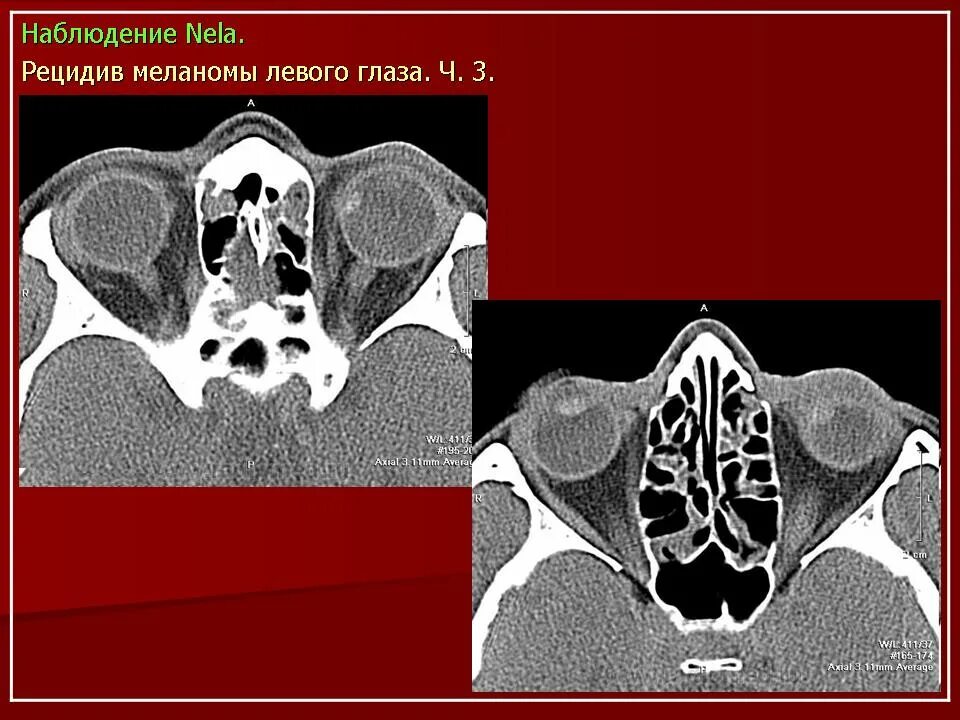

Данные кт